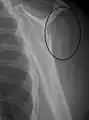

A fracture of the greater tuberosity as seen on AP X ray

A fracture of the greater tuberosity of the humerus